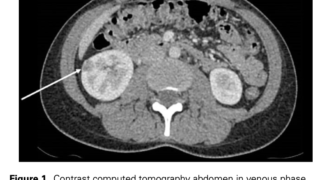

特に非小細胞肺癌、乳癌、多発性骨髄腫、頭頸部の扁平上皮癌、卵巣癌、腎臓癌で多い。

原因

PTHrP産生腫瘍 80% (humoral hypercalcemia of malignancy : HHM)

扁平上皮癌(特に肺、頭頸部)、尿路上皮癌(腎癌、膀胱癌)、乳癌、非ホジキンリンパ腫、卵巣癌など。

骨溶解性転移 20% (local osteolytic hypercalcemia : LOH)

乳癌、多発性骨髄腫がほとんどを占める。